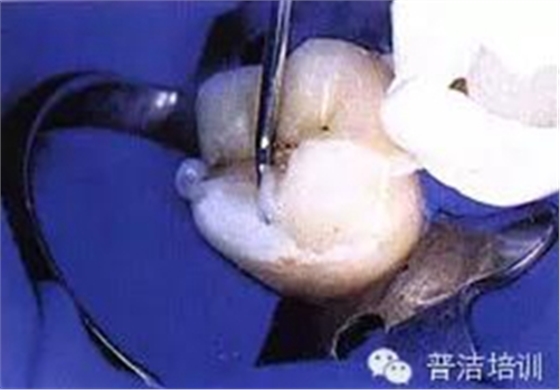

二、去除齲壞的組織,可以使用送風(fēng)公司生產(chǎn)的齲齒檢測液來判斷齲壞的組織是否去除干凈

三、牙體預(yù)備完成,,邊緣預(yù)備短斜面(45度),短斜面這點很多書上沒具體說,想想還是有必要的,但在金屬嵌體和瓷嵌體就沒必要了。其實預(yù)備這一步驟沒什么高深莫測的,多加訓(xùn)練,端正態(tài)度就可以。